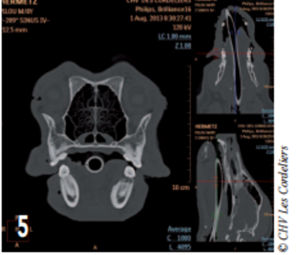

Le scanner a révélé la présence d’une lyse osseuse de l’os alvéolaire mandibulaire s’étendant de la racine dorsale de la carnassière jusqu’à la racine caudale de la deuxième prémolaire (photos 2 à 6).

Photo 5 : La lyse osseuse de la mandibule commence sous la couronne dentaire de la racine rostrale de la carnassière.